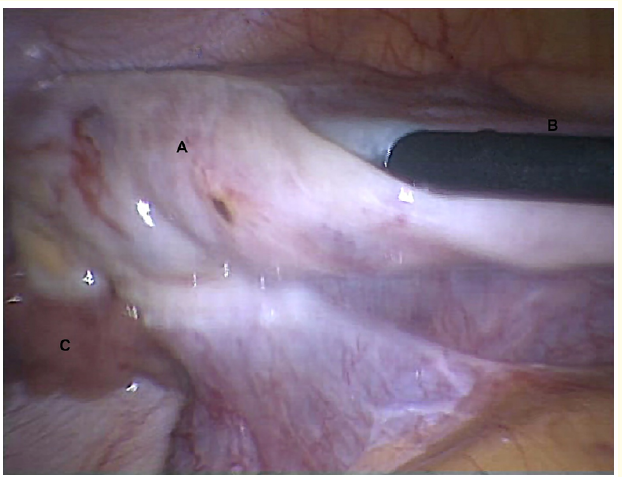

The Rare Abnormality of Fallopian Tube: A Case Report

Svetlana O Dubrovina, Aleksander Shiring, Vitaliy Gimbut and Oksana Ardintzeva. 12(6): 64-67.